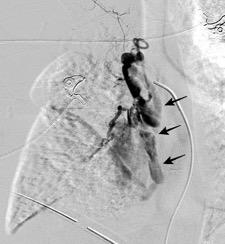

Quiste hidatídico.

Comunica con el hiato esofágico y el espacio pararrenal anterior.

Colecciones “inflamatorias” abdominales llegan al tórax vía el hiato esofágico o por vía transdiafragmática

Afectación transdiafragmática: 5,6-43,7% de quistes hepáticos. “Área desnuda” del hígado.

Panda A et al. “Straddling Across Boundaries”. Thoracoabdominal Lesions: Spectrum and Pattern Approach. Curr Probl Diagn Radiol. 2015 Área desnuda. El hígado en contacto directo con el tendón central del diafragma. Contiene el hiato de VCI.

Pedrosa I et al. Hydatid Disease: Radiologic and Pathologic Features and Complications. Radiographics 2000